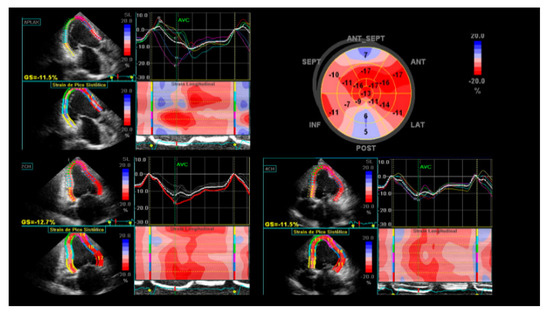

- Barbosa, M.M.; Rocha, M.O.C.; Vidigal, D.F.; de Carvalho Bicalho Carneiro, R.; Araújo, R.D.; Palma, M.C.; de Barros, M.V.L.; Nunes, M.C.P. Early detection of left ventricular contractility abnormalities by two-dimensional speckle tracking strain in Chagas’ disease. Echocardiography 2014, 31, 623–630. [Google Scholar] [CrossRef]

- García-Álvarez, A.; Sitges, M.; Regueiro, A.; Poyatos, S.; Pinazo, M.J.; Posada, E.; Bijnens, B.; Heras, M.; Gascon, J.; Sanz, G. Myocardial deformation analysis in Chagas heart disease with the use of speckle tracking echocardiography. J. Card. Fail. 2011, 17, 1028–1034. [Google Scholar] [CrossRef]

- Gomes, V.A.; Alves, G.F.; Hadlich, M.; Azevedo, C.F.; Pereira, I.M.; Santos, C.R.; Brasil, P.E.; Sangenis, L.H.; Cunha, A.B.; Xavier, S.S.; et al. Analysis of Regional Left Ventricular Strain in Patients with Chagas Disease and Normal Left Ventricular Systolic Function. J. Am. Soc. Echocardiogr. 2016, 29, 679–688. [Google Scholar] [CrossRef]